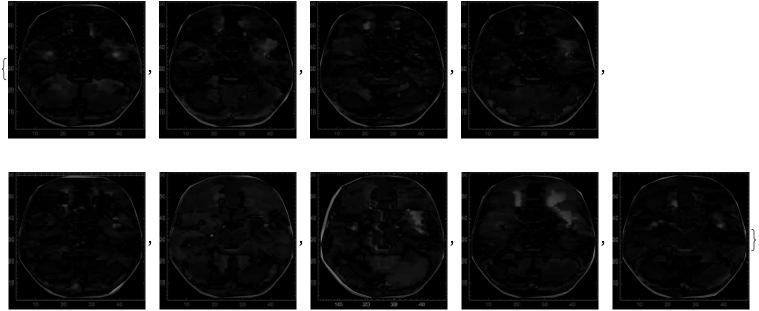

Next, we can find the image difference between the mean and the activity plot for each of the 360 words:

In[]:=

averageDifferenceLLM=​​Table[​​ImageDifference[​​ImageResize[Image[ArrayPlot[Table[​​current=embedding[tokenizer[listOfWords[[x]]]];current=List[Last[layer[current]]];current,{layer,decoderLayers}][[;;,1,;;]][[;;,756;;768]]]],{550,550}],​​ImageResize[meanLLMActivity,{550,550}]],{x,1,360}];

A section for these results of the first 5 words against the mean is shown.

Table[​​ImageDifference[​​ImageResize[Image[ArrayPlot[Table[​​current=embedding[tokenizer[listOfWords[[x]]]];current=List[Last[layer[current]]];current,{layer,decoderLayers}][[;;,1,;;]][[;;,756;;768]]]],{550,550}],​​ImageResize[meanLLMActivity,{550,550}]],{x,1,5}]

Out[]=

We can then plot the image difference between the mean and each participant:

averageDifferencefMRI=Table[ImageDifference[ImageResize[grayImagesOfScans[[x]],{550,550}],ImageResize[grayMeanScan,{550,550}]],{x,1,9}]